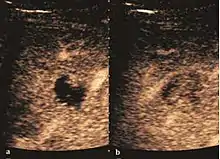

- Liver cyst

- Hydatid liver cyst. Diagnostic criteria are the presence of membranes and sediment inside.